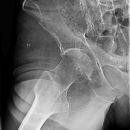

Hüfte nach Lauenstein I (45°)

Qualitätskriterien

Gute Beurteilung des Hüftkopfes, der Pfanne und des Schenkelhalses. Der Trochanter major überdeckt weitgehend den Schenkelhals.